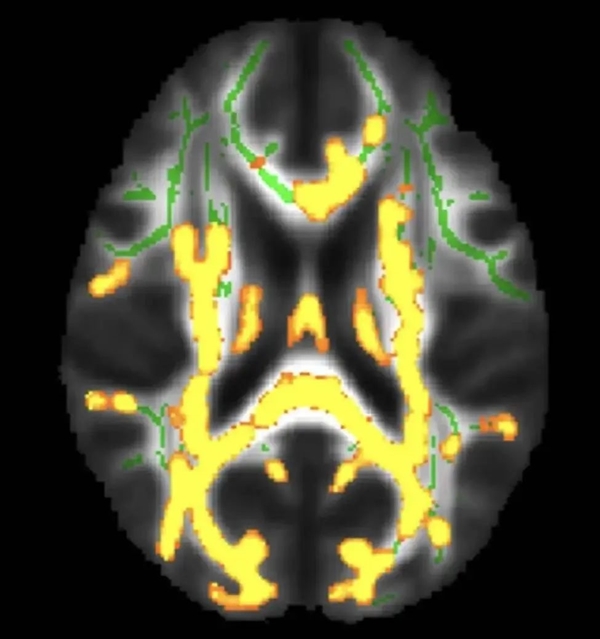

隐藏的内脏脂肪水平较高,神经炎症(黄色)增加 图源:丁香医生